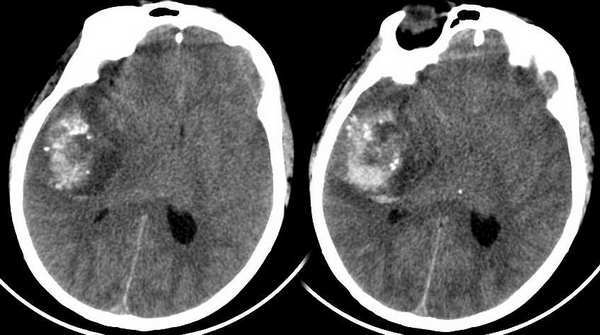

男性,46岁,平时无症状,今突发头痛来就诊!

右颞叶类圆形高密度影,其外上部可见散在更高密度钙化点,考虑海绵状血管瘤破裂出血。

颅内肿块较大,病灶内有钙化及出血,周围水肿却不明显,而病人平时无症状,首先考虑海绵状血管瘤可能大。

颅内肿块较大,周围水肿却不明显,必须考虑临床头痛出现是颅内出血后的伴发还是颅内占位所致?而病人平素无症状,个人观点认为海绵状血管瘤较胶质瘤可能大。

avm并发出血可能大,因钙化呈散在斑点状,且病灶较大不太符合 海绵状血管瘤

只能说是颅内占位病变伴出血,脑疝形成,至于是血管畸形还是胶质瘤或脑膜瘤,依据不足,可以问病史,阅老片,或是病情稳定后增强。临床目前也不会关心到底是什么性质的肿瘤。